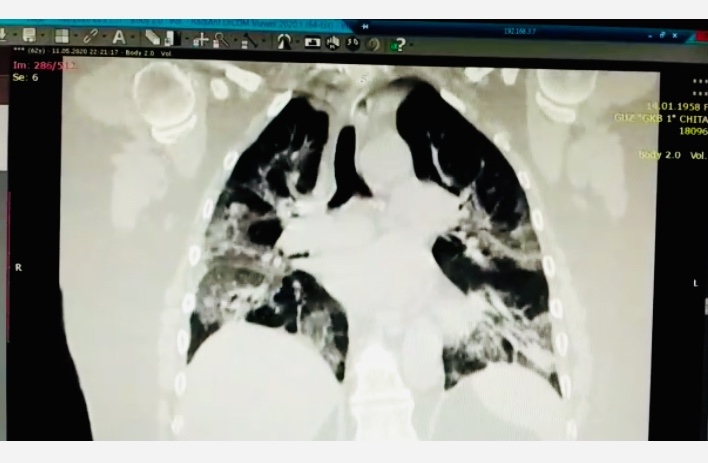

«На фото - тотальное поражение легких новым коронавирусом. Белые участки - это и есть болезнь. Лёгкие не могут выполнять свои функции и участвовать в газообмене. Врачи называют это синдромом "булыжной мостовой" или "лоскутного одеяла". Из-за тотального поражения лёгких у пациента развивается состояние гипоксемии: очень низкого уровеня напряжения кислорода в крови. При этом страдают все органы, прежде всего головной мозг. Кроме того, участки поражения лёгких не являются каким-то инертным субстратом, они содержат гигантское количество воспалительных веществ (цитокинов), которые разносятся по организму с кровью вызывая отказ внутренних органов, провоцируя образование тромбов. Это называется "цитокиновый шторм", - резюмирует доктор.

Заключение о представленном клиническом случае. Больная женщина с первого дня госпитализации была подключена к аппарату искусственной вентиляции лёгких, которые имели массированное поражение. К большому сожалению, несмотря на все усилия врачей, спасти человека не удалось.